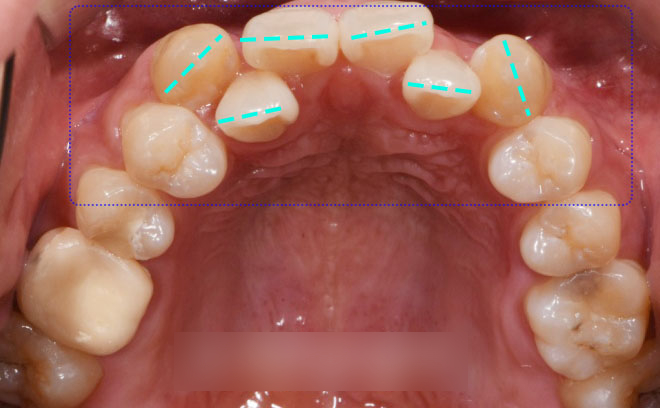

가지런하지 못한 앞니 치열도

눈에 띄었는데요.

이 부분은 총생으로

삐뚤빼뚤 정렬되지 못한 배열을 말하며,

특히 전치부에서 흔하게 나타납니다.

먼저 부족한 공간을 만들어 내기 위해서는

치아가 이동할 수 있는 유격을

만들어야 됐습니다.

필요한 공간을 만드는 과정은

발치로 진행이 되었는데요.

이렇게 공간 부족일 경우에

겹친 곳들을 해소하여 확보를 합니다.